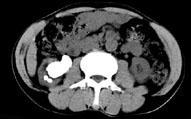

问题 男,53岁,反复右侧腰部隐痛不适2年余,CT如图所示,下列说法正确的是 ( )

选项 A、右肾自截 B、部分肾盏有扩张积液 C、右肾铸型结石 D、右肾钙化 E、右肾多发结石

答案 BCE